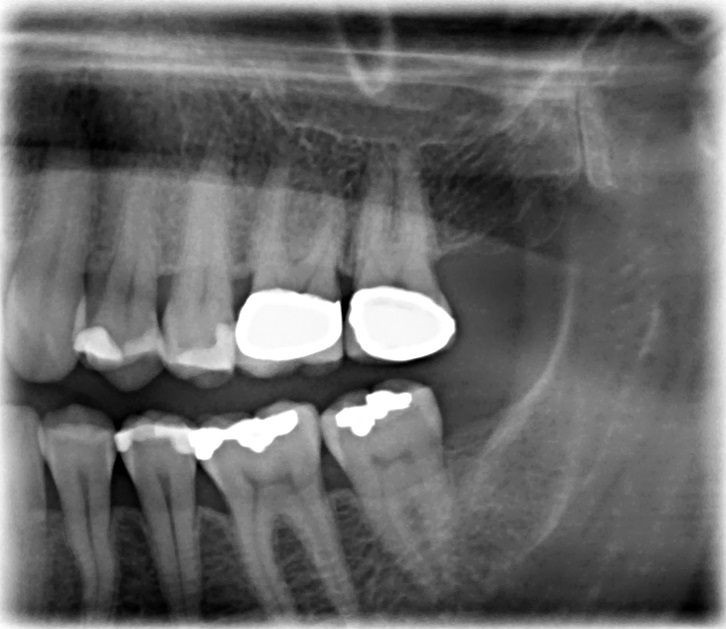

– 36er (langjährige Amalgamfüllung) → seit einiger Zeit gefühlt etwas empfindlicher als sonst auf Reize, insbesondere leichte Empfindlichkeit auf Warmes/Heißes, jedoch keine Aufbissschmerzen

– 26er/27er (beide überkront) → seit einiger Zeit ebenfalls leichte Empfindlichkeit auf Warmes/Heißes zwischen beiden Zähnen (gefühlt eher am 27er)

– 25er → Ziehen (gefühlt im Bereich des Zahnhalses/-zwischenraums), keine gesteigerte Empfindlichkeit auf Reize und keine Aufbissschmerzen

– 46er (langjährige Amalgamfüllung) → ebenfalls ein Ziehen im Bereich der Füllung

Ich habe ziemlich schmerzempfindliche Zähne, auch aufgrund freiliegender Zahnhälse und Knirschen (trage nachts eine Unterkieferschiene). Beim Zahnarzt wurden zwei OPG-Bissflügelaufnahmen gemacht (siehe anbei). Es seien keine aktuell behandlungsbedürftigen Auffälligkeiten zu sehen. Es wurde oben und unten im Bereich der Zahnbeschwerden kürettiert. Entzündete Zahnzwischenräume sollen Ursache für die Beschwerden sein mit Empfehlung zu einer PZR. Ich reinige meine Zähne zusätzlich mit Zahnseide und Interdentalbürsten, das Zahnfleisch blutet jedoch nicht. Daher meine Fragen:

3.) Sehen Sie am 16er (bis auf die überfüllte Wurzelfüllung) noch eine Entzündung?

23-27 & 34-37:

13-17 & 44-47:

keine erkrankung sichtbar auf foto und röntgenbildern.